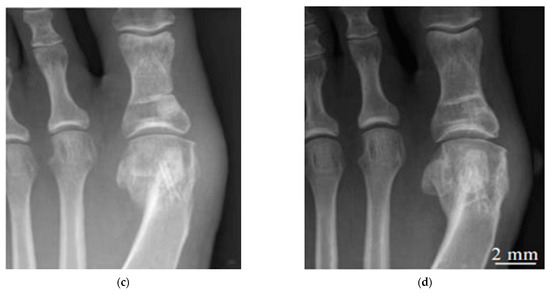

- Plaass, C.; von Falck, C.; Ettinger, S.; Sonnow, L.; Calderone, F.; Weizbauer, A.; Reifenrath, J.; Claassen, L.; Waizy, H.; Daniilidis, K.; et al. Bioabsorbable Magnesium versus Standard Titanium Compression Screws for Fixation of Distal Metatarsal Osteotomies—3 Year Results of a Randomized Clinical Trial. J. Orthop. Sci. 2018, 23, 321–327. [Google Scholar] [CrossRef]

| Mg-Y-RE-Zr screws | Bunion orthopaedics | 40 | Germany | 79% healing after 6 weeks, 90% healing after 12 weeks | [202] |